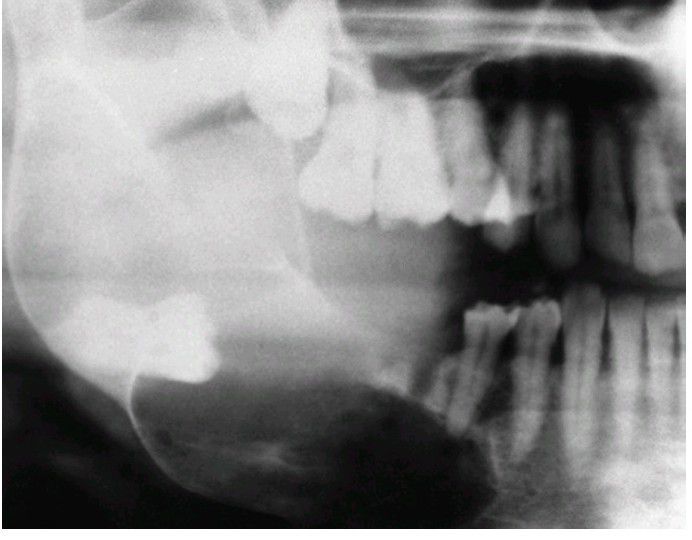

Dentigerous cyst

Large dentigerous cyst that extends from the coronoid process to the mental foramen. The cyst has displaced the impacted third molar to the inferior border of the mandible.